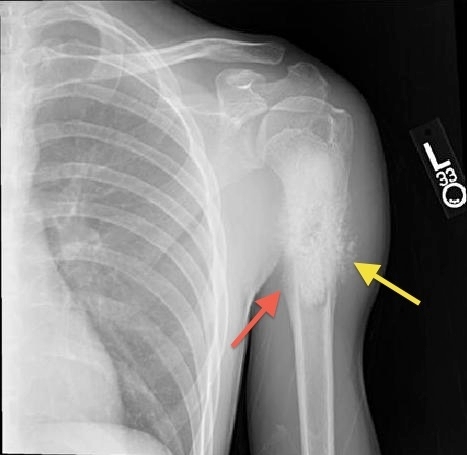

The patient most likely has osteosarcoma, the most common primary bone tumor affecting children and young adults. Boys between ages 13 and 16 years are at higher risk. In children, the tumor occurs most frequently at the metaphyses of long bones such as the distal femur, proximal tibia, and proximal humerus. Constitutional symptoms such as fever, weight loss, and malaise are usually absent. On physical examination, the most important finding is a tender soft-tissue mass. Characteristic x-ray findings include a spiculated "sunburst" pattern (yellow arrow) and periosteal elevation known as the Codman triangle (red arrow). Alkaline phosphatase and lactate dehydrogenase are elevated from turnover of damaged osteocytes; high levels may correlate with adverse prognosis. Increased erythrocyte sedimentation rate is a non-specific marker of inflammation. Treatment includes tumor excision and chemotherapy.